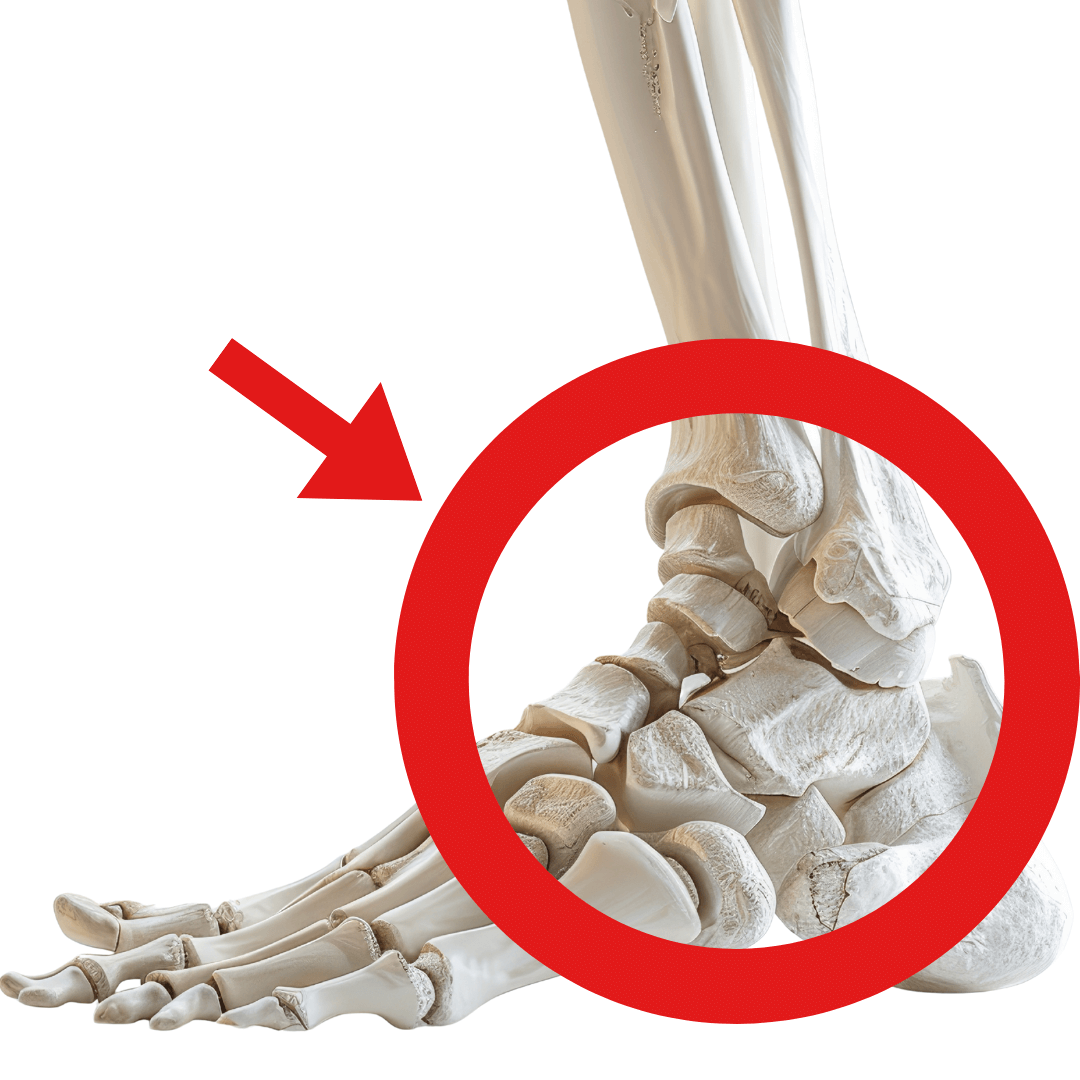

足首の関節の可動不全

最も見落とされやすいのが、足首の動きです。

足首の関節と言っても、足指を除いて7つの関節があります。

それぞれに役割があり、複雑に関係しあっています。

背屈              底屈

項目         (つま先を上げる)   (つま先を下げる)

正常な動き          20度                        45度

障害がある場合    10度以下                  30度以下

足首の動きが悪いと、歩行時に膝が代償動作を行い、負担が増加します。

実は「変形性膝関節症」の方の99%が、これら3つの関節に問題を抱えています。